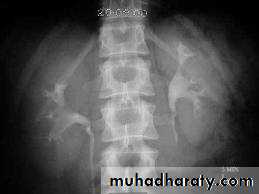

A. First a plain x-ray of the abdomen is taken before the injection of the contrast media, also known as A KUB (kidney, Ureter and Bladder). Calcification & stones may be obscured & missed by contrast media if plain film not takenfirst .B. Films taken after injection of contrast’ medium:

1.Nephrogram phase (Immediately after injection of contrast) .